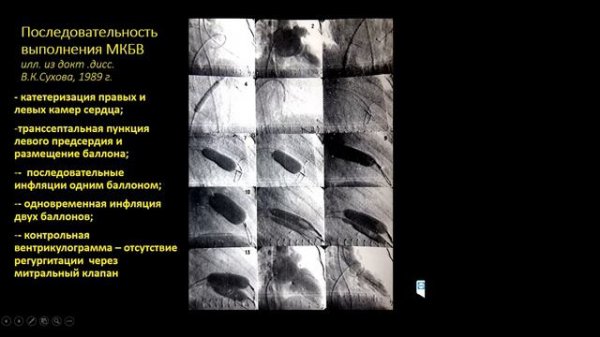

Лекция №13. Пороки створчатых клапанов сердца: проблемы диагностики и лечения